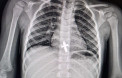

Як розповідає лікар-ендоскопіст та хірург дитячий Олександр Сльозко, проковтування монет дітьми – поширене явище. Такі випадки трапляються регулярно, подекуди й до 10 на тиждень. У квітні лікарям також довелося ендоскопічно діставати з бронхів підлітків цвях та канцелярську кнопку, а зі стравоходу дворічної дитини – натільний хрестик.